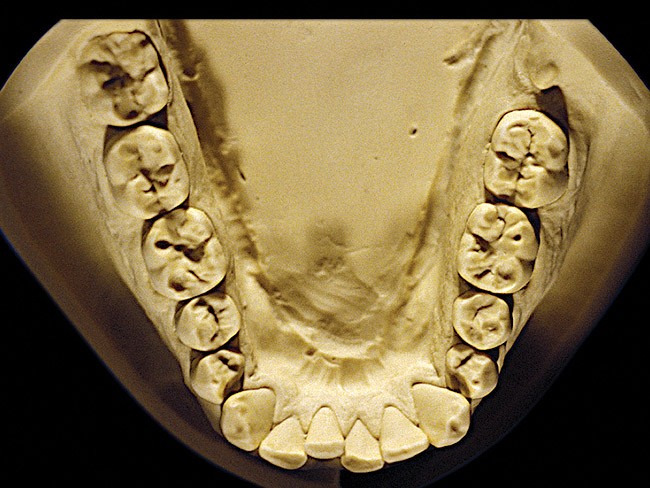

Figure 8  Moderate NCLTS from toothpaste, mandibular arch.

Figure 8

Figure 7 and Figure 8 are examples of NCLTS resulting from toothpaste. Upon examination, one could see that the overall anatomical detail of the teeth was faded with a sandblasted appearance. A closer view of the facial surfaces (Figure 9 and Figure 10) illustrates this to a greater degree and one can observe that the normal intricate facial anatomy was completely missing. It is interesting to note there was no cervical recession of the gingiva, even though every surface of every tooth had been abraded. This is due to the fact that this patient had always used a soft, round-ended filament toothbrush.21-22 This patient's sole desire regarding her oral hygiene was to get her teeth whiter.

So that the previous example is not misleading, the behavioral profile of the toothpaste abuser is not necessarily the "caries-free immaculate oral hygiene patient," but can be virtually anyone who brushes their teeth with toothpaste. Figure 11 and Figure 12 illustrate a more advanced example of toothpaste abuse showing a patient with multiple restorations and some unkempt teeth. The anatomical details were faded with a sandblasted appearance and the silver alloy restorations were highly polished. The facial surfaces of the mandibular canines and premolars were affected the most, creating the pathognomonic pattern. Figure 13 and Figure 14 are a close-up view of this area, illustrating a cupping or cratering effect, but of the asymmetrical variety. This patient did not like the color of his teeth and spent an inordinate amount of time brushing his teeth. Again, likewise due to the exclusive use of a round-ended, soft-bristle toothbrush, note there was no cervical gingival recession in this case either. When the featured casts illustrating toothpaste abuse (Figure 7, Figure 8, Figure 9, Figure 10, Figure 11, Figure 12, Figure 13 and Figure 14) were hand-articulated, the worn surfaces did not match up and the diagnosis of toothpaste abuse was confirmed.